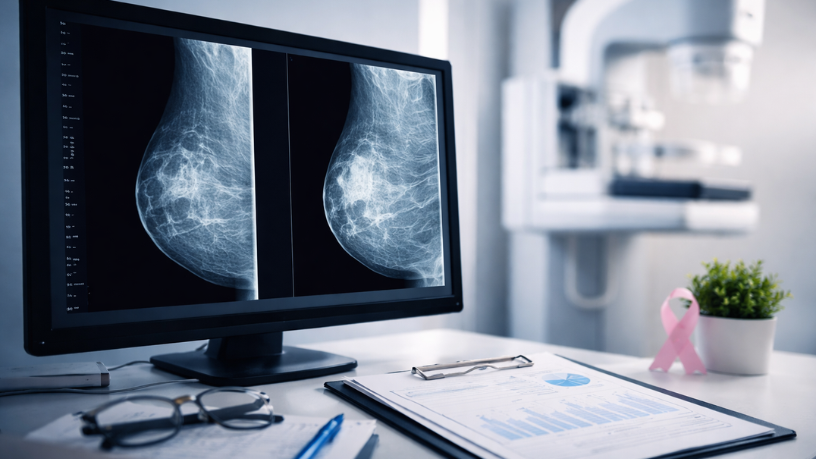

A mamografia utiliza tecnologia radiológica capaz de produzir imagens detalhadas das mamas. Vinicius Tadeu Sattin Rodrigues explica que o exame permite visualizar diferentes estruturas presentes no tecido mamário, como componentes glandulares, fibrosos e adiposos. Cada um desses tecidos apresenta características específicas nas imagens obtidas durante o exame.

Essa diferenciação ajuda o radiologista a interpretar as estruturas observadas nas mamas. A análise detalhada das imagens permite identificar padrões que contribuem para a avaliação clínica. Nesse contexto, a mamografia se torna uma ferramenta importante na investigação da saúde mamária.

Durante a análise das imagens, diferentes características do tecido mamário podem ser observadas. Entre os elementos identificados estão nódulos, pequenas calcificações e variações na densidade das mamas. Na avaliação de Vinicius Tadeu Sattin Rodrigues, cada uma dessas estruturas é analisada cuidadosamente para compreender sua natureza. O especialista observa formato, distribuição e comportamento das imagens.